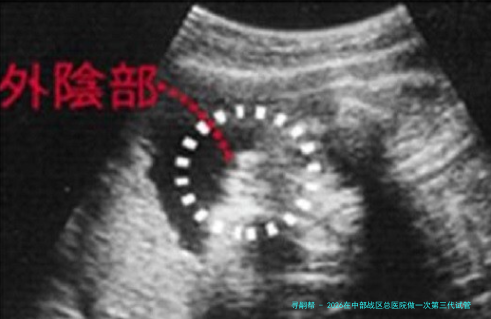

胚胎活检与筛查:对发育至囊胚期的胚胎进行活检,样品送检验进行遗传课程分数析。